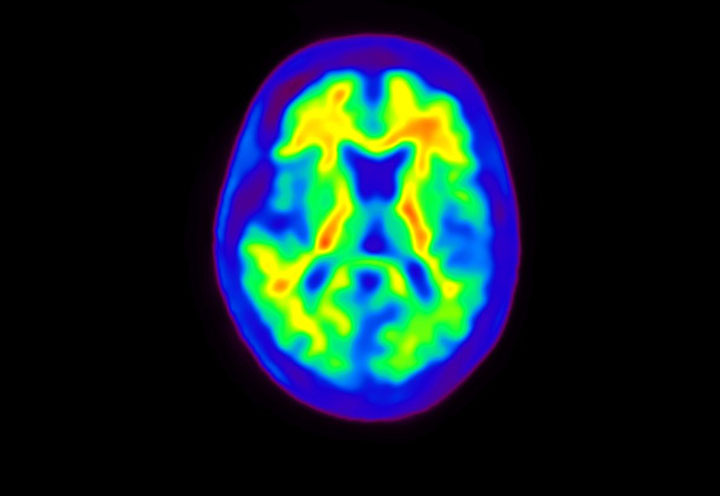

Head / Case4 : Amyloid

Coronal

Courtesy : Kindai University Hospital

- Imaging protocol

- Injected dose: 3.21 MBq/kg, 18F-Flutemetamol

- Uptake time: 100 minutes

- Scan time: 20 minutes